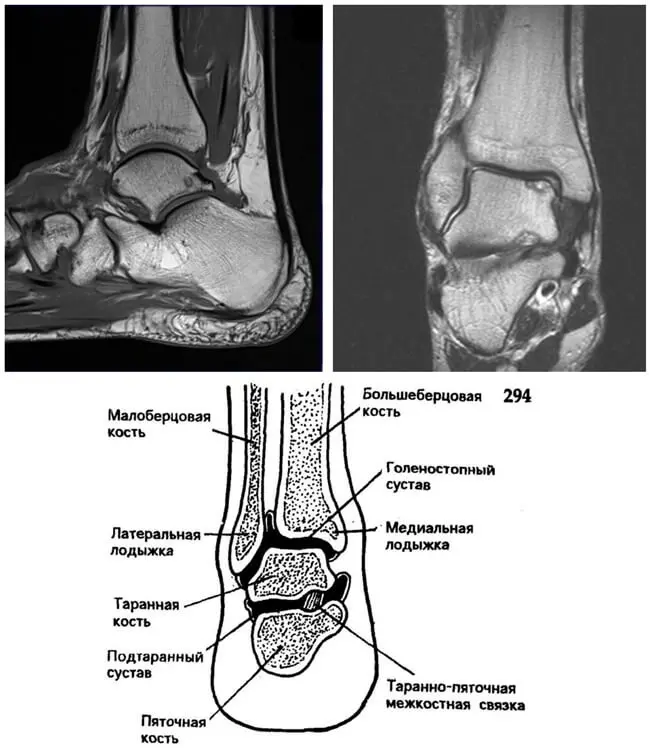

МРТ гомілковостопного суглоба

Гомілковостопний суглоб нерідко пошкоджується при незручному русі в момент ходьби або бігу. Гомілковостопний суглоб має складну будову, оскільки складається з трьох кісток.

Для дослідження гомілковостопного суглоба використовують не тільки рентген, але і МРТ. Причому, саме МРТ гомілковостопного суглоба допомагає встановити гранично точний діагноз.